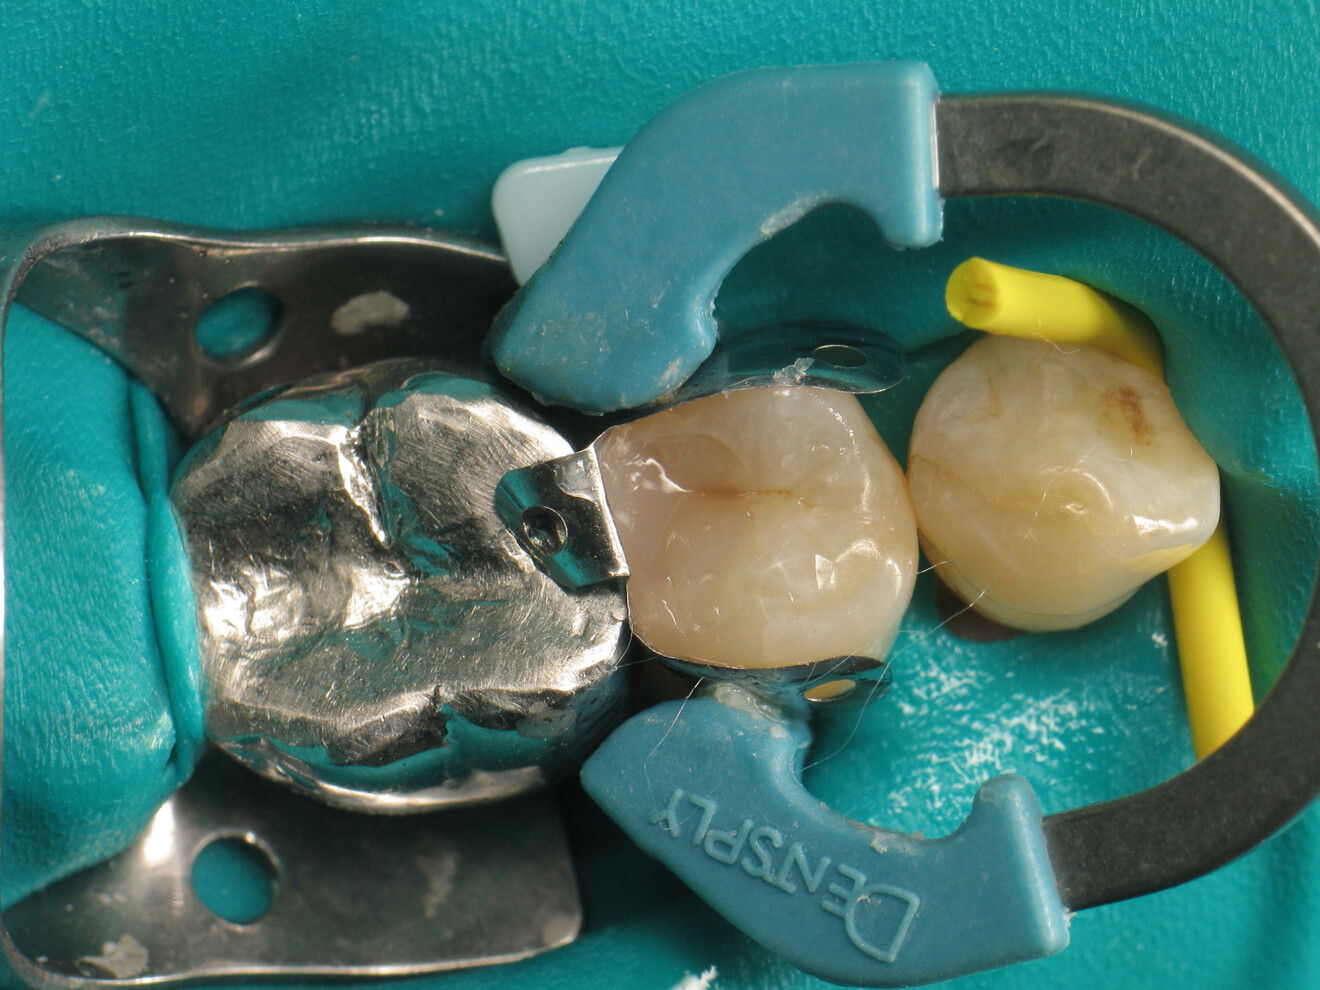

Fig. 4: Placement of the proximal matrix.